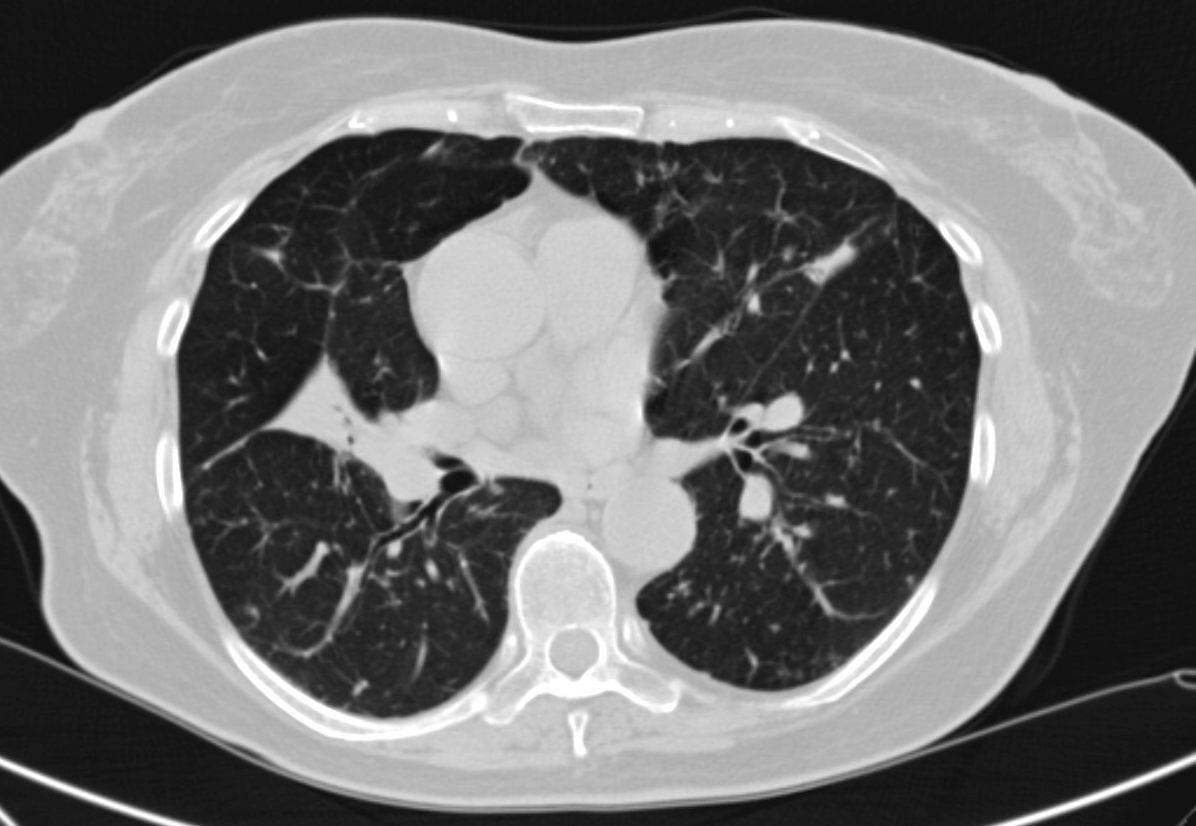

4: Miliary pattern: sarcoidosis, CT, lung window. Axial image and sagittal reformat.

A 67 year old female suffering from COPD. Bilateral rough branching interstitial widening and patchy, miliary nodules with perihilar dominance along the bronchovascular fibres and the fissures.